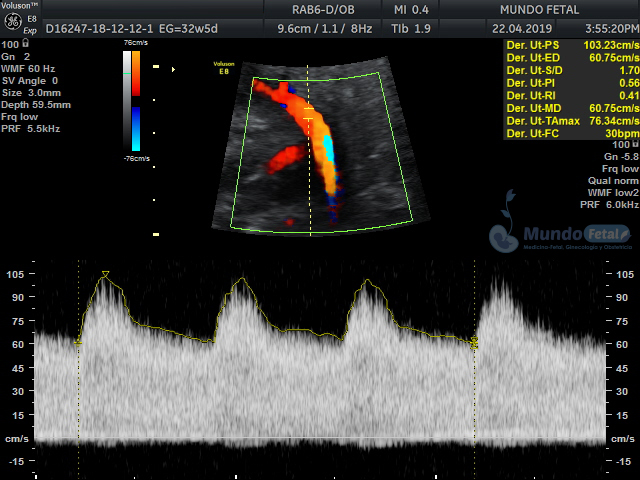

Se recomienda de 32-34 semanas, realizando valoración de crecimiento armónico (4 medidas específicas), valoración anatómica, líquido amniótico, flujos sanguíneos fetales y placentarios perfilando el bienestar fetal hacia el final de embarazo.